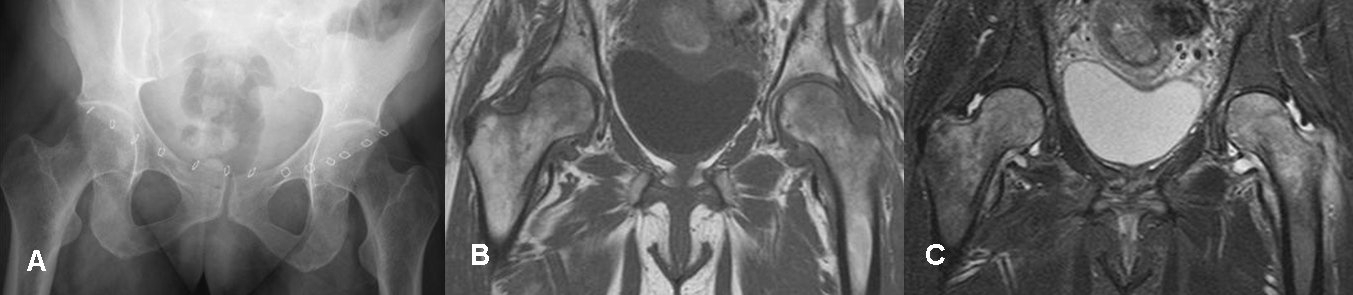

Fig 55. Artritis infecciosa.

A: Rx AP. Disminución del espacio articular en el lado izquierdo, al comparar con el contra-lateral.

B: RM coronal en STIR. Edema óseo en la cabeza femoral y acetábulo, por artritis séptica. Severos cambios inflamatorios en los componentes del cuadriceps y los glúteos, sin formación

de colecciones.

Fig 59. Osteoporosis transitoria.

A: Rx AP. Paciente post-cesárea, con dolor en ambas caderas. Se aprecia moderada osteopenia, en las cabezas femorales.

B: RM coronal en T1 y C: RM coronal en STIR. Edema en ambas cabezas femorales, con moderado derrame asociado.